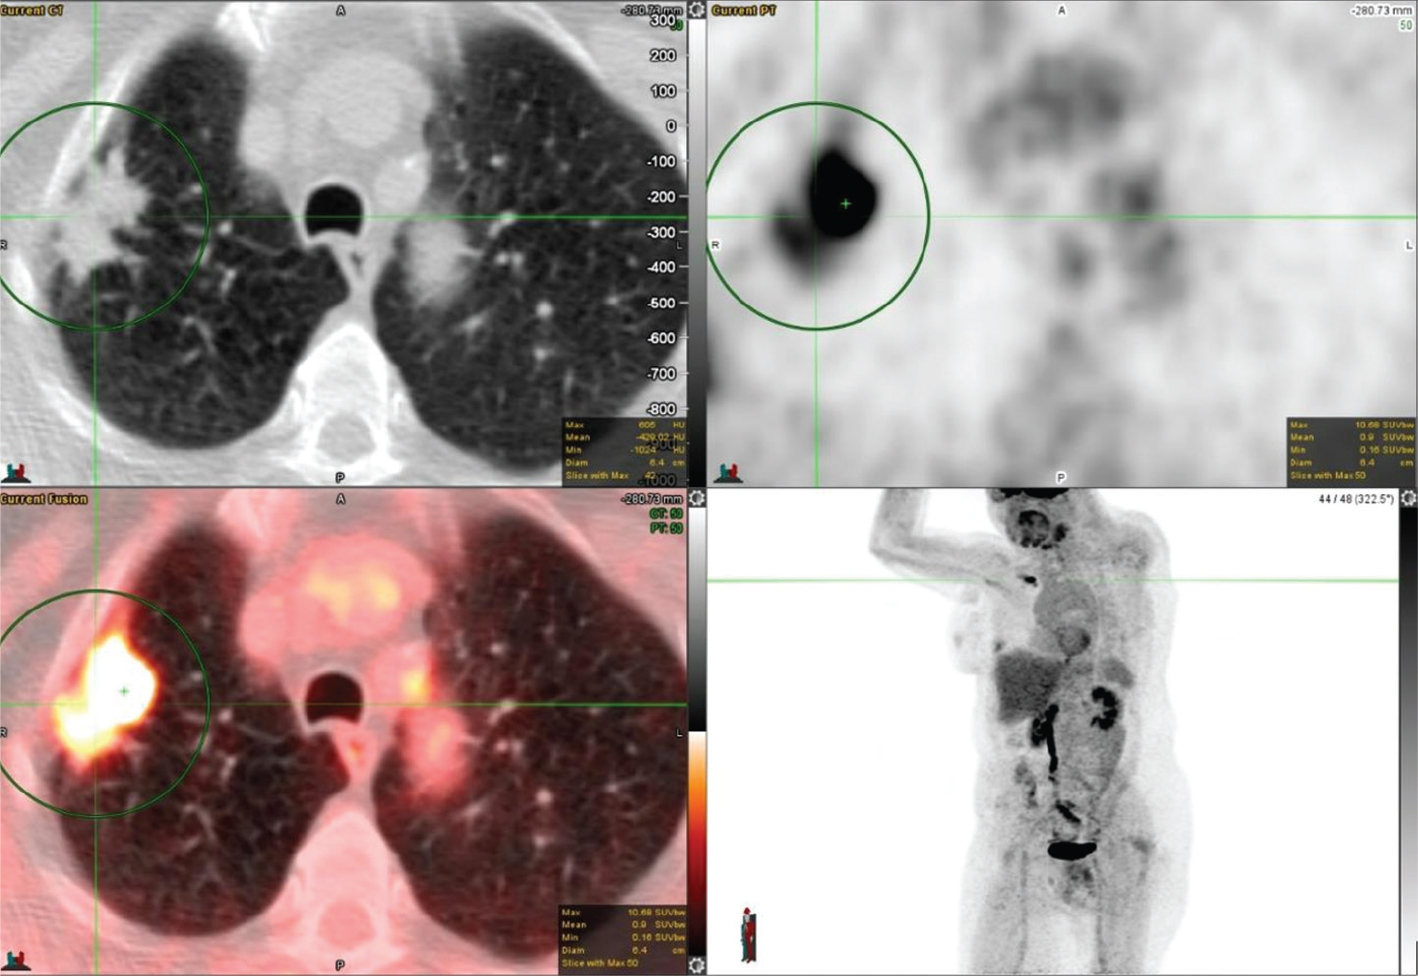

18F-FDG PET/CT demonstrates excellent performance in classifying SPNs as benign or malignant. Combining anatomical and metabolic imaging is synergistic by maintaining the sensitivity of CT and the specificity of PET, resulting in an overall significantly improved accuracy. 18F-FDG PET/CT can ultimately lead to considerable cost savings by reducing the number of biopsies and surgical interventions. Not all patients can undergo biopsy due to comorbidities or not being a surgical candidate or inaccessible to bronchoscopy. In such a scenario, radiation oncologists may prefer to treat lesions based on PET findings and clinical evaluation without biopsy confirmation. Furthermore, a pulmonary nodule in a patient with a known primary malignancy could represent a metastatic nodule of that primary malignancy, as shown in Figure 2.

Fig 2

Figure 2. Breast cancer with metastatic pulmonary nodules. FDG PET/CT images include axial CT (top left panel), axial PET (top right panel), fused axial PET/CT (bottom left panel), and PET image with maximum intensity projection (MIP) (bottom right panel). In the green circle, there is a small sub-centimeter left upper lobe pulmonary nodule with mildly increased FDG uptake (SUV max of 3.7) above the background of the mediastinal blood pool. There were additional sites of FDG-avid pulmonary nodules and breast nodules (not included on the PET/CT images though some can be seen on the MIP image) that were most suspicious of metastatic disease.